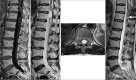

Figure 3:

Preoperative sagittal and axial spinal magnetic resonance imaging demonstrating a cystic lesion near the conus medullaris. (a) Sagittal T1-weighted image with non-contrast sequence. (b) Sagittal T2-weighted image. (c) Axial T2-weighted image. (d) Postoperative sagittal T2-weighted image 2 years after surgery reveals complete regression of the dilation (white bold arrow).